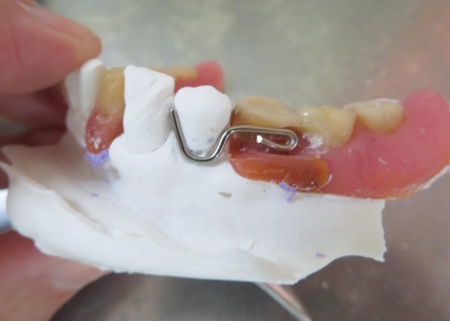

外側のクラスプの位置を確認しました

内側のクラスプの位置を確認しました